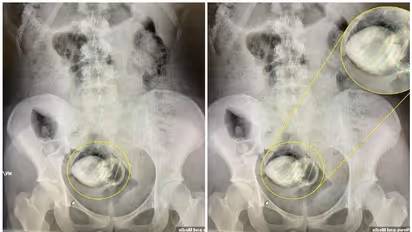

അവരാണ് ആശുപത്രിയിൽ പോകാൻ നിർദ്ദേശിച്ചതെന്നും ഡെയിലി മെയിൽ റിപ്പോർട്ട് ചെയ്തു. അങ്ങനെ തന്റെ റൂംമേറ്റുമായി ആശുപത്രിയിലേക്ക് പോകാൻ തീരുമാനിച്ചത്. തുടർന്ന് അവിടെ വച്ചെടുത്ത എക്സ്-റേയിൽ സെക്സ് ടോയ് കുടുങ്ങി കിടക്കുന്നതായി കണ്ടെത്തിയത്. ക്രിസ്റ്റൽ കൊണ്ട് അലങ്കരിച്ചതായിരുന്നു സെക്സ് ടോയ്. ഡോക്ടർമാർക്ക് കൈകൊണ്ട് തന്നെ സെക്സ് ടോയ് നീക്കം ചെയ്യാൻ കഴിഞ്ഞു.